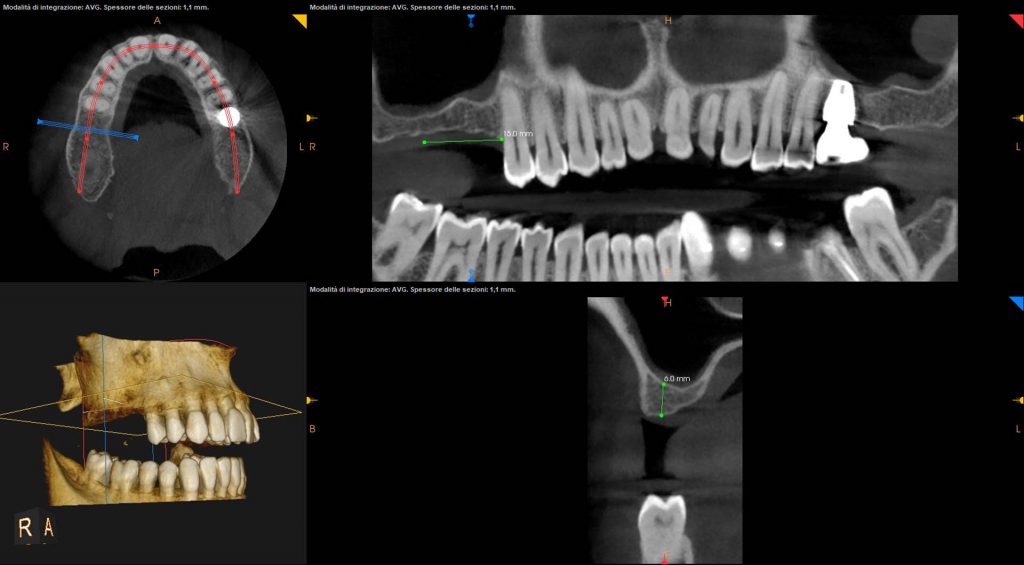

I stopped at about 2 mm from the maxillary sinus floorIn this case, since the distance between the crest and the floor is of about 8 mm in #16 area and 6mm in 17# area, a 6 mm stop is inserted on the first implant and a 4mm stop on the second.

Pre-op and post-op CBCT have been obtained with my Carestream 8100. In addition to providing us with very defined images, this device allows performing CBCT of only three teeth. This greatly reduces the radiation dose for the patient.